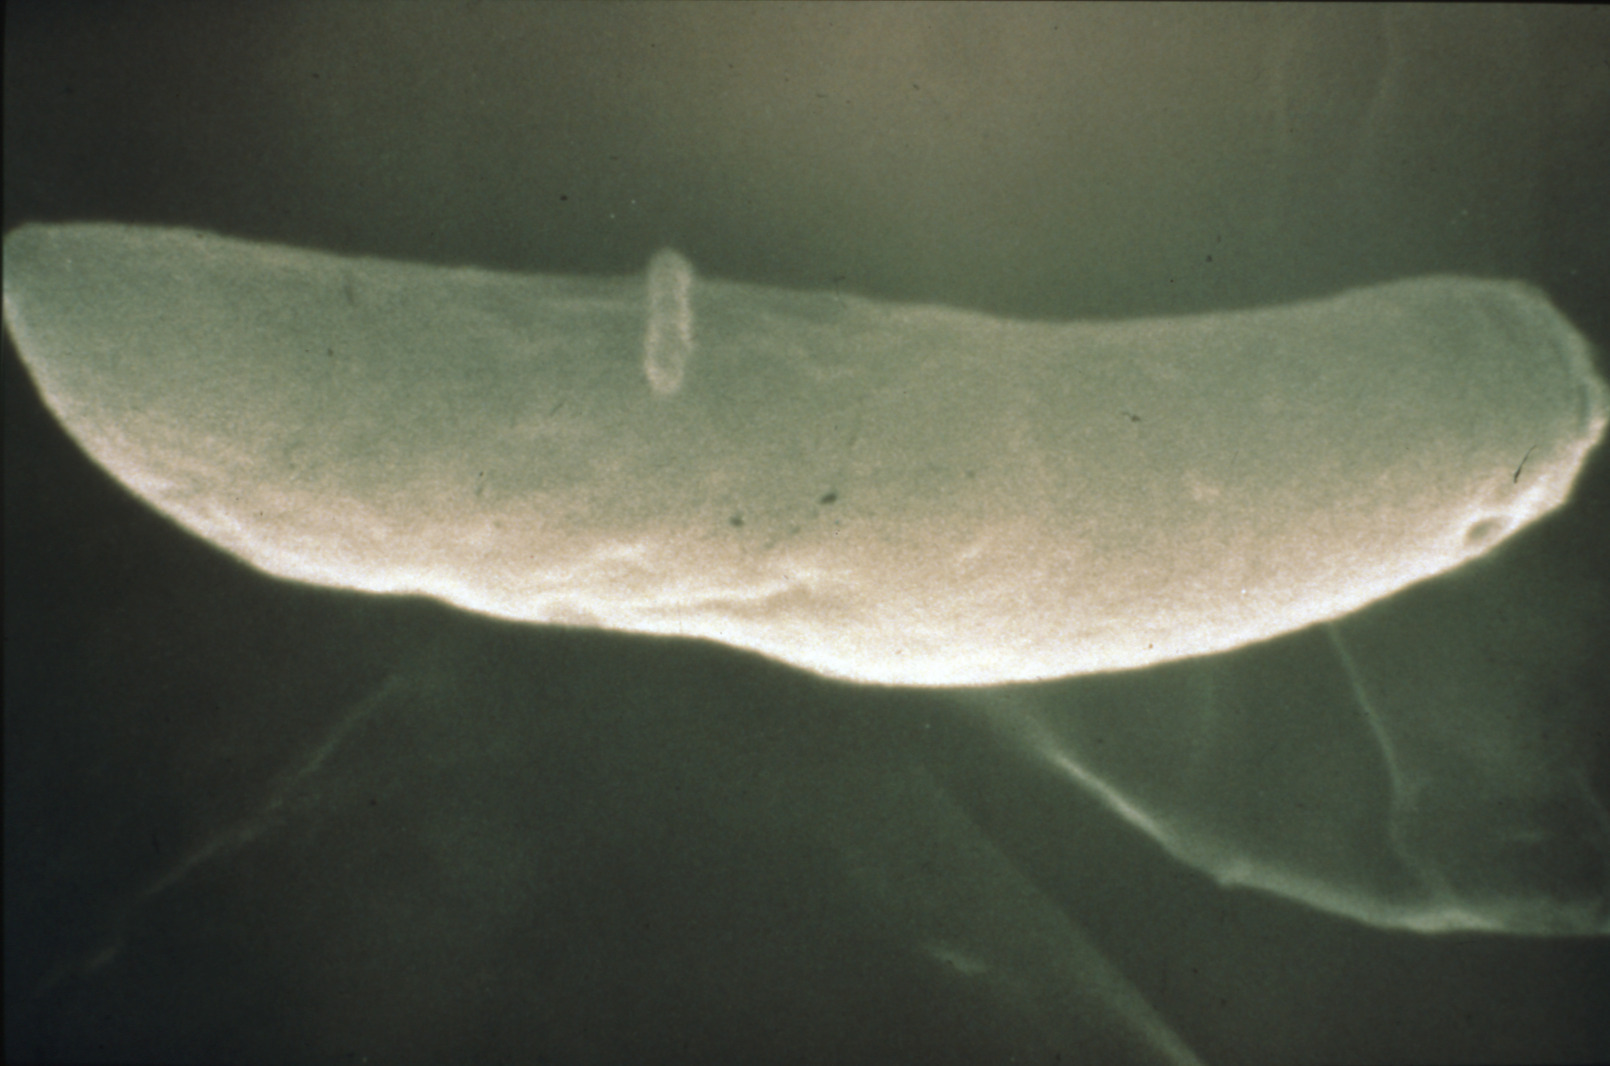

Coccidiosis in chickens and turkeys (slide study set no. 7)

Avian coccidiosis Avian medicine Chickens--Diseases Turkeys--Diseases